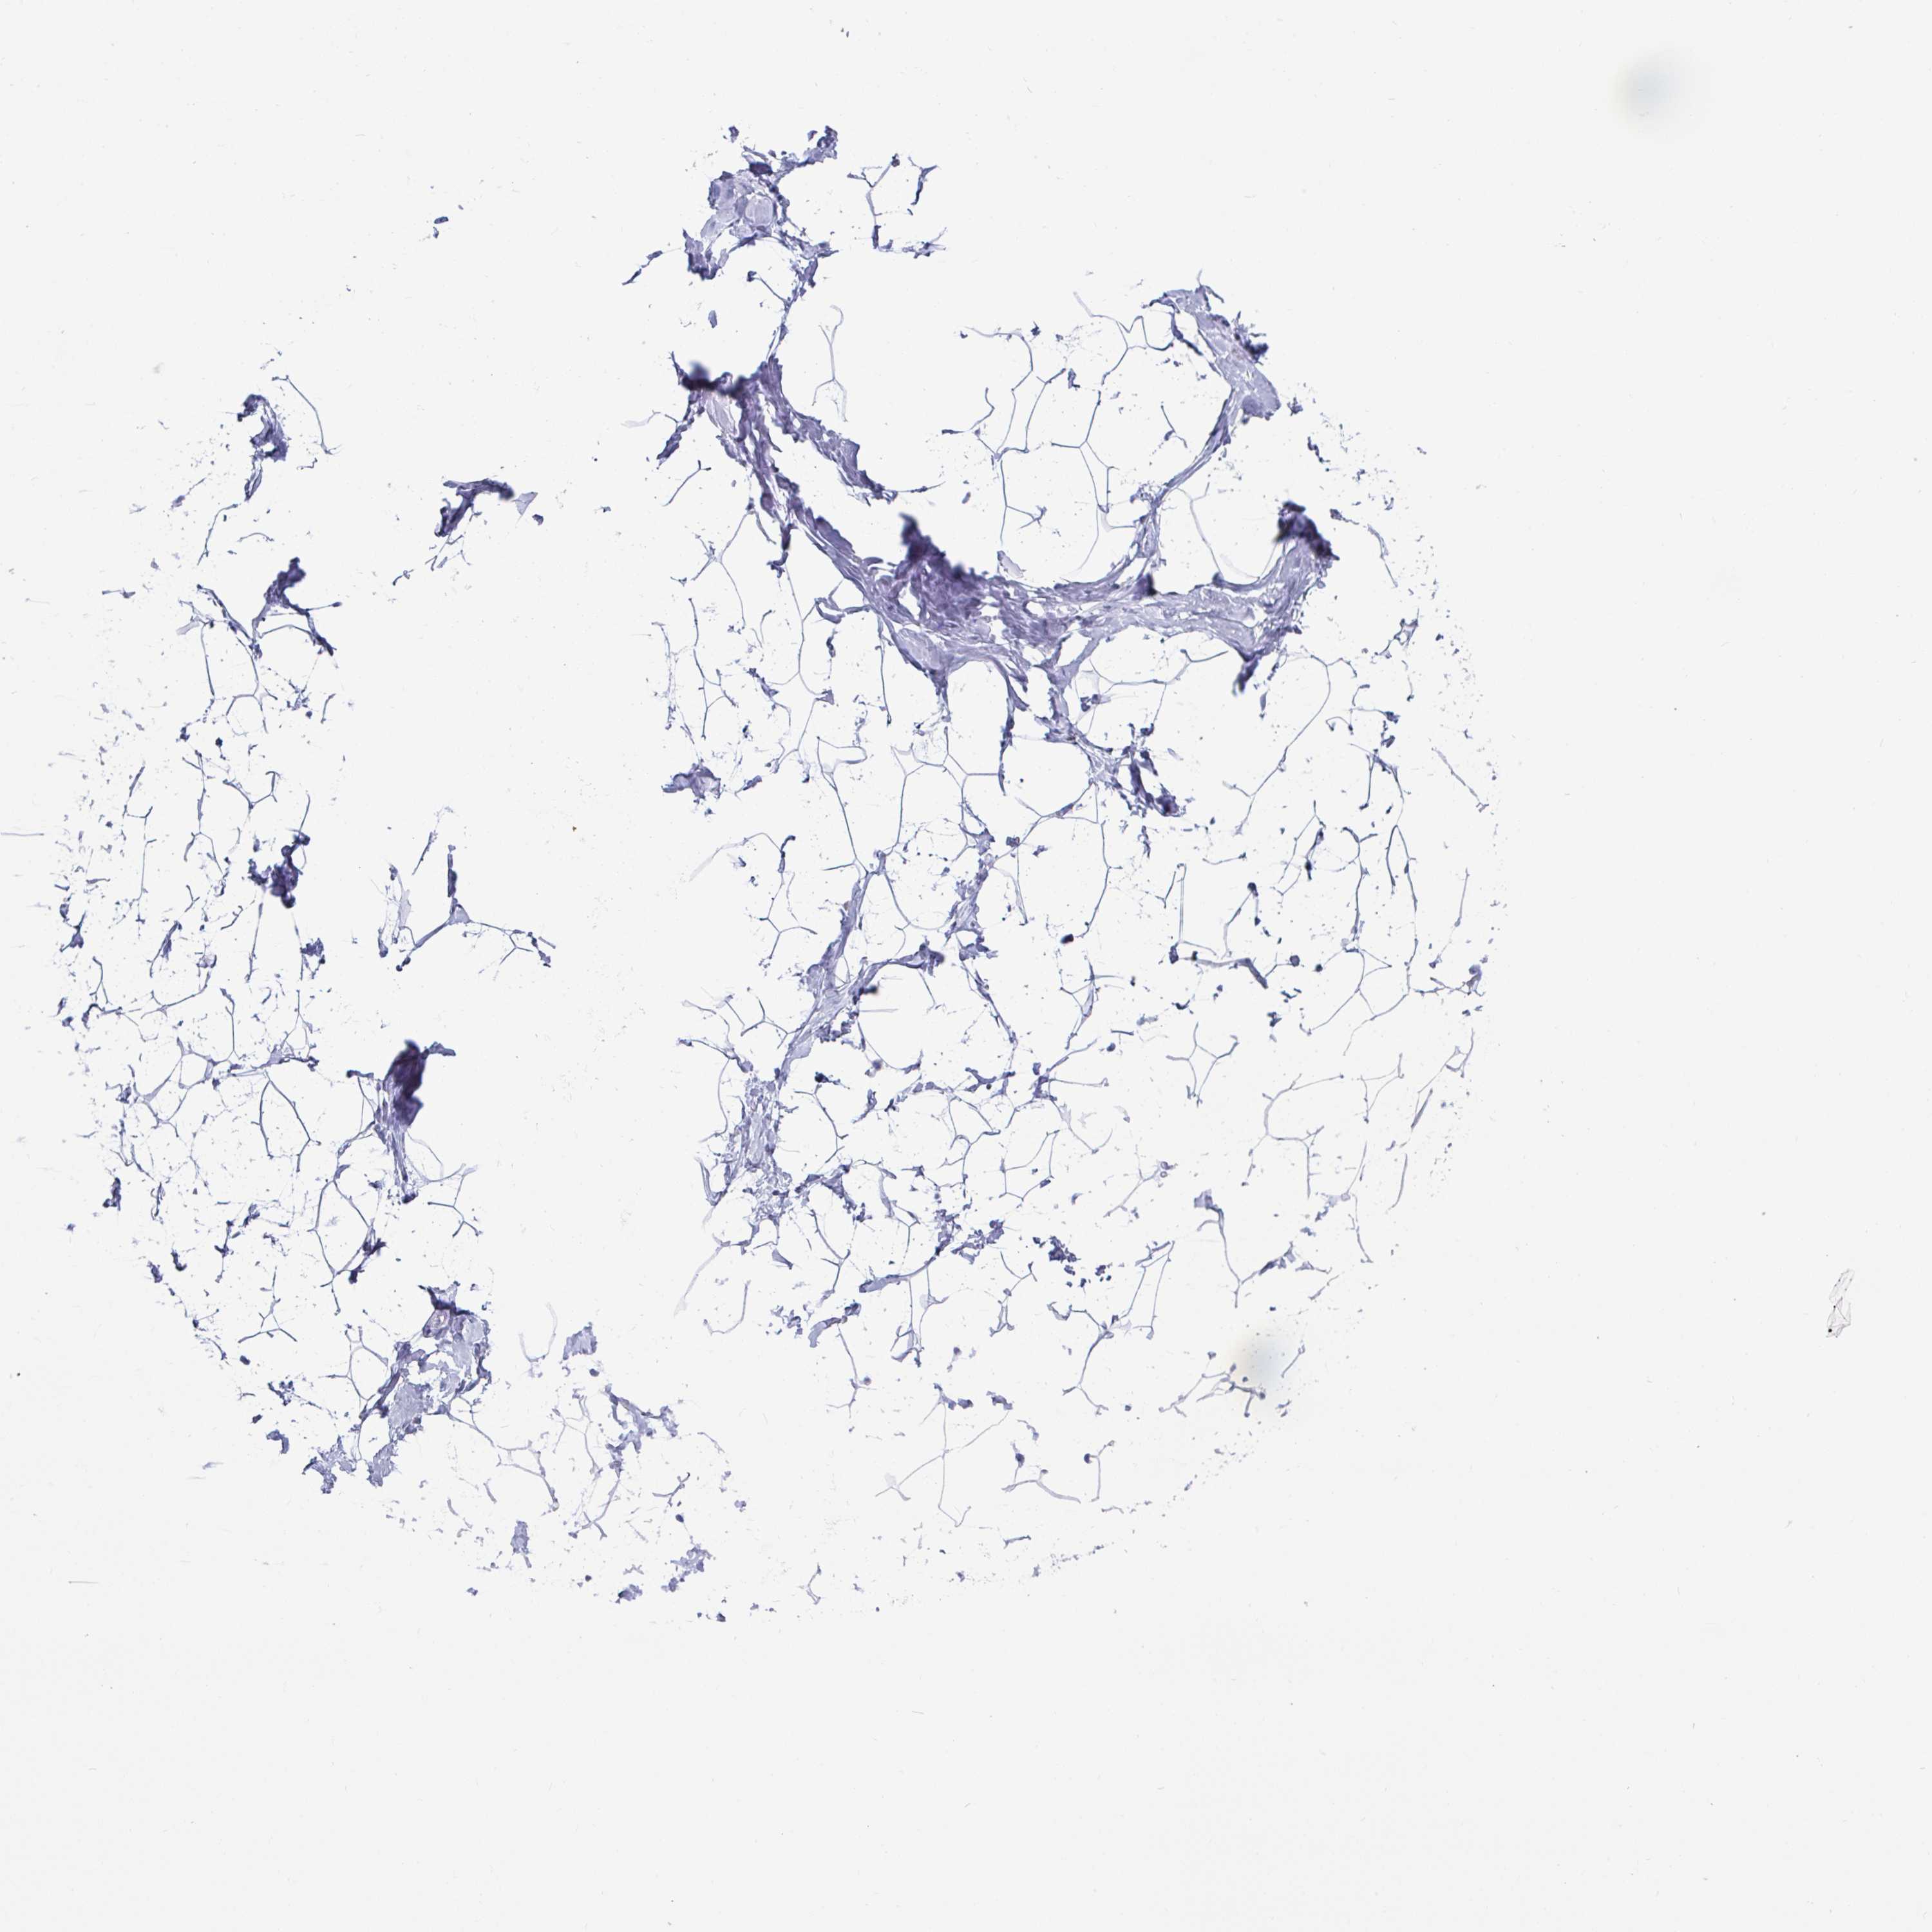

BREAST - Antibody stainingi

Antibody staining in the annotated cell types in the current human tissue is reported as not detected, low, medium, or high, based on conventional immunohistochemistry profiling in selected tissues. This score is based on the combination of the staining intensity and fraction of stained cells.

Each image is clickable and will lead to virtual microscopy that enables deeper exploration of all samples and also displays staining intensity scores, fraction scores and subcellular localization as well as patient and tissue information for each sample.

Antibody HPA038224

Adipocytes Not detected

Glandular cells Not detected

Myoepithelial cells Not detected